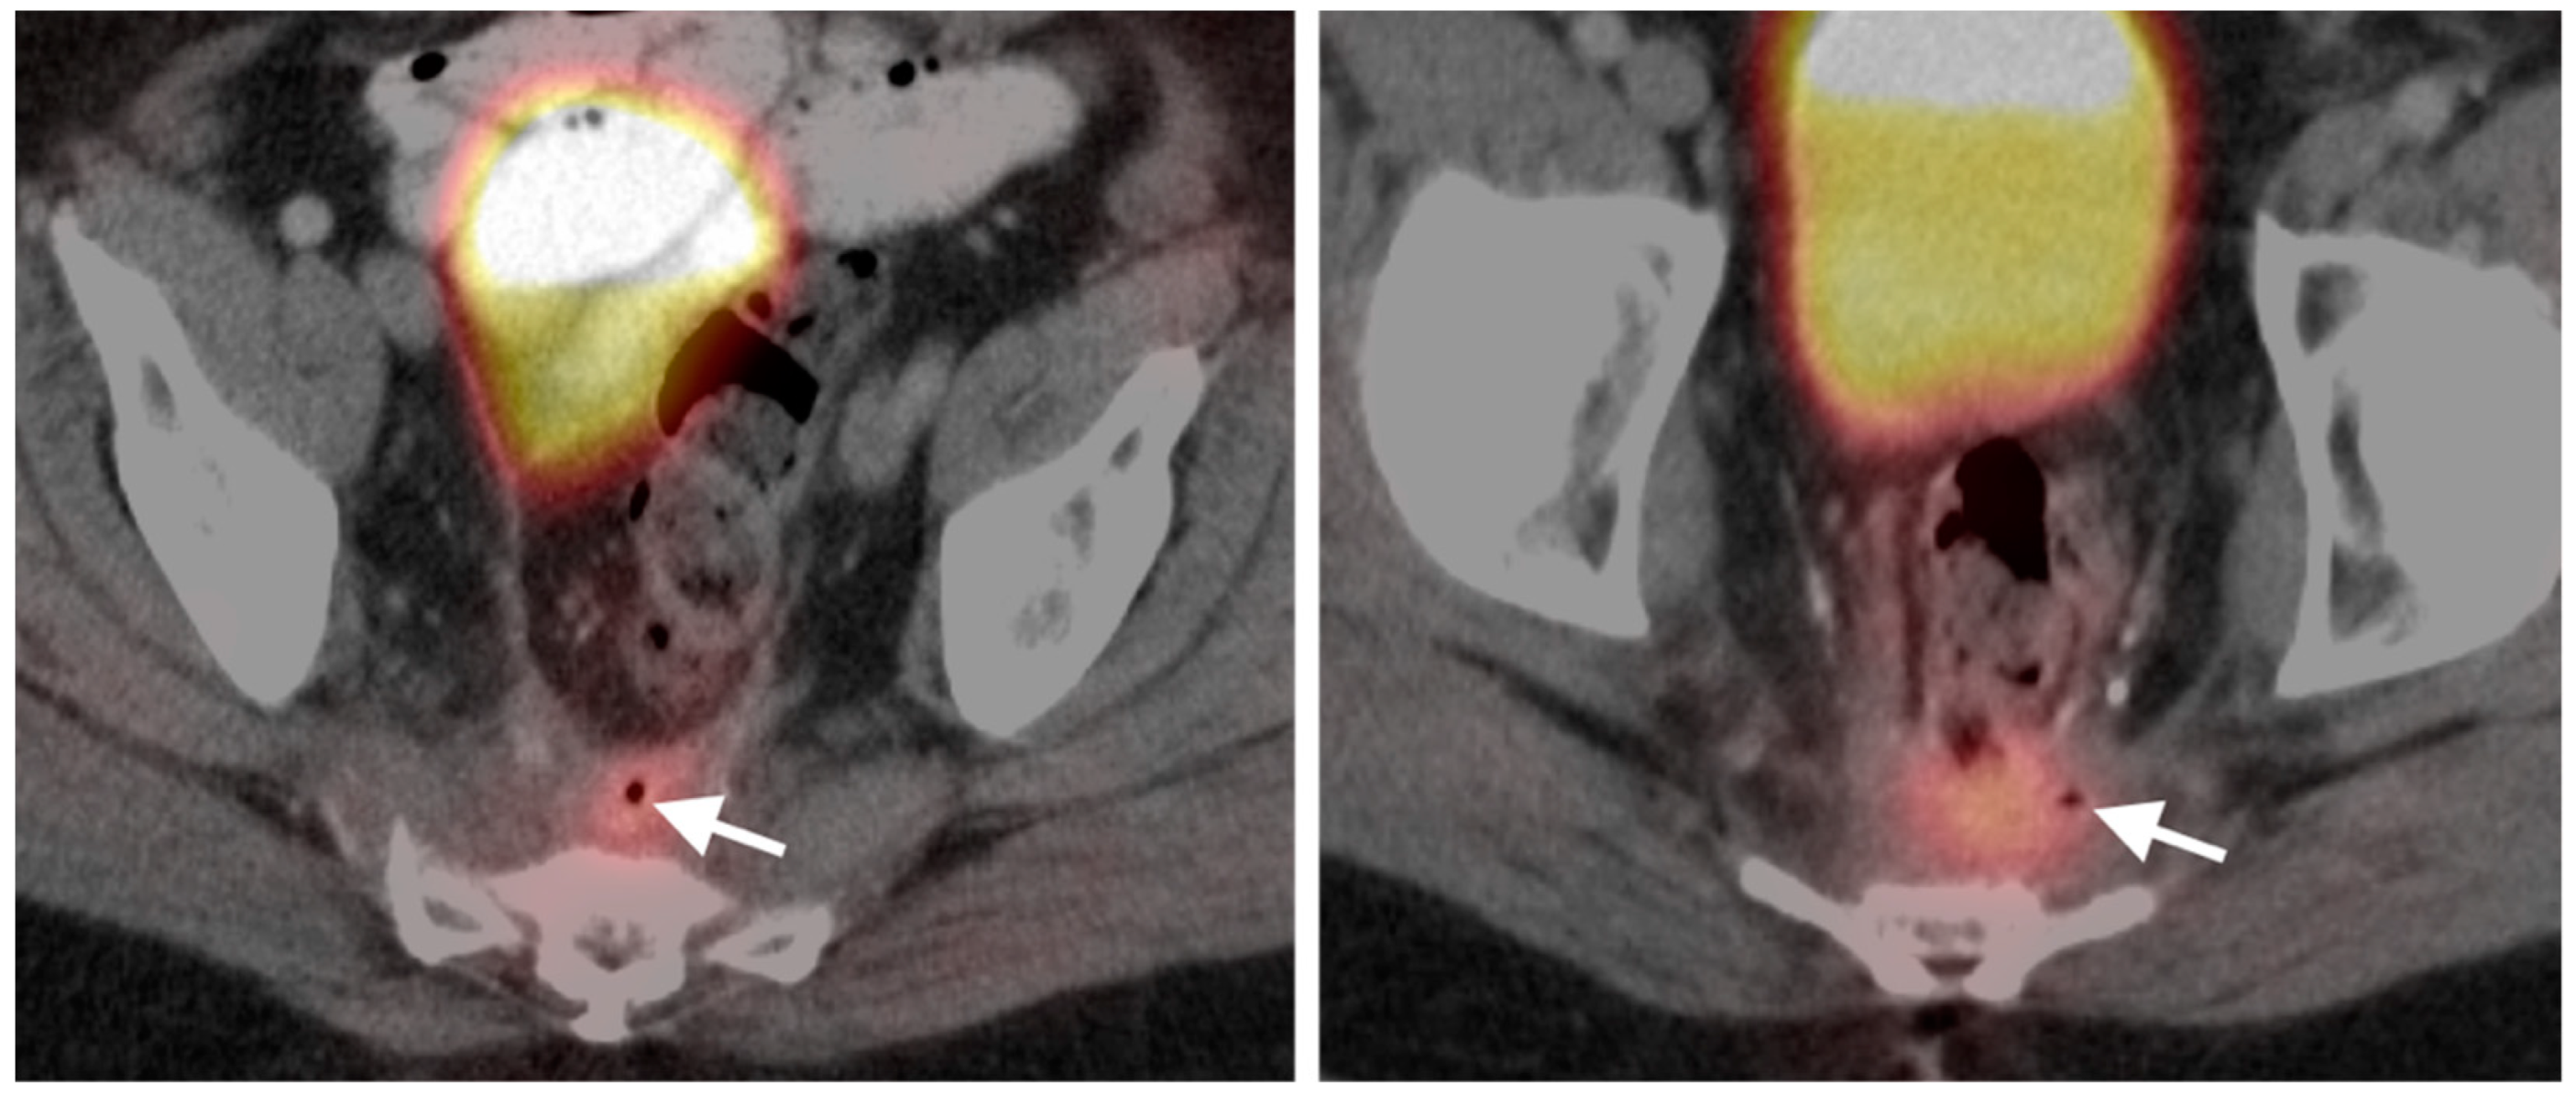

9. Bowel Adenocarcinoma: Colon, Rectum, Small Bowel